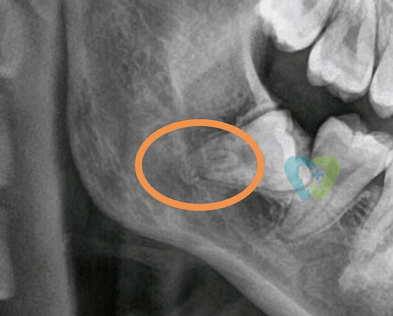

文章图片

术前全景片局部

通过CBCT发现 , 右侧下颌这颗埋在颌骨内的智齿 , 不仅两个牙根融合在一起 , 且根尖弯曲 , 弯曲处刚好卡着下颌神经管 。

牙根弯曲拔除容易断根 , 再加上紧贴下颌神经管 , 一旦拔除动作过大 , 可能损伤神经管 , 导致嘴唇、下巴周围皮肤和下颌牙产生麻木感或感觉迟钝 , 严重时甚至会造成永久性损伤 。